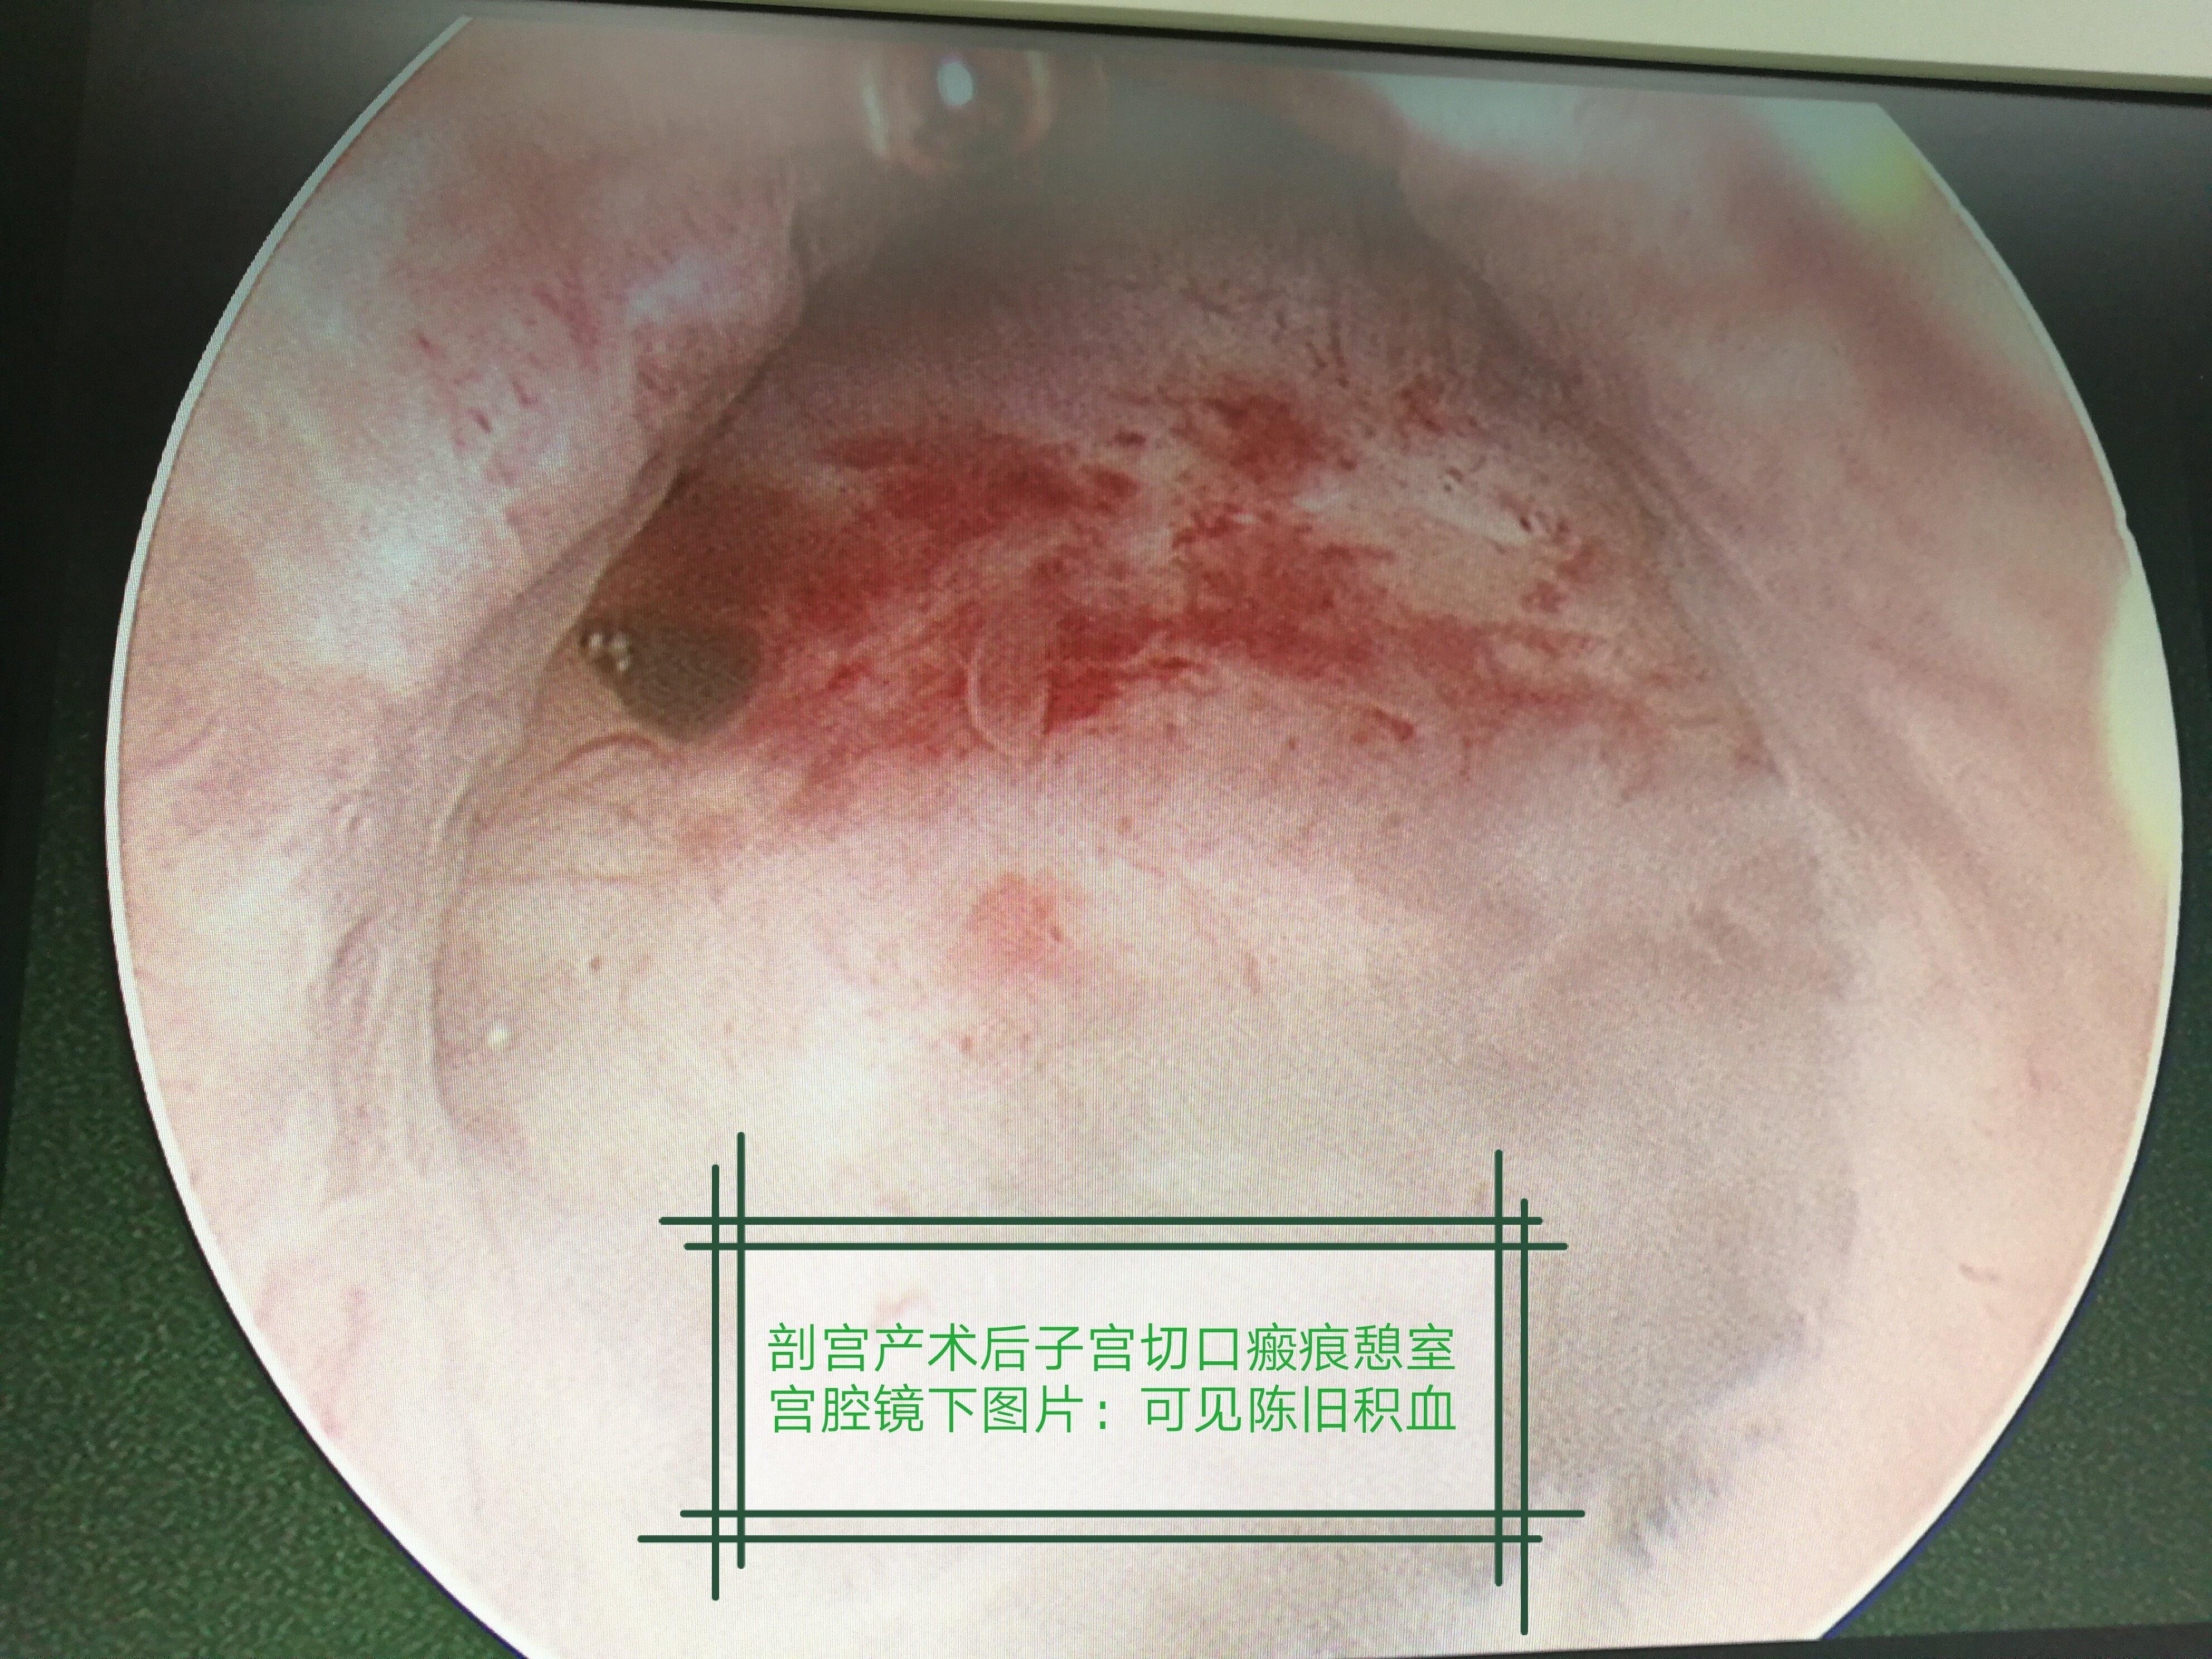

剖腹产切口憩室图片

手术解析宫腔镜下切除剖宫产术后子宫切口憩室

憩室,被定义为子宫下段肌层内的低回声区,这反映了既往剖宫产子宫切口